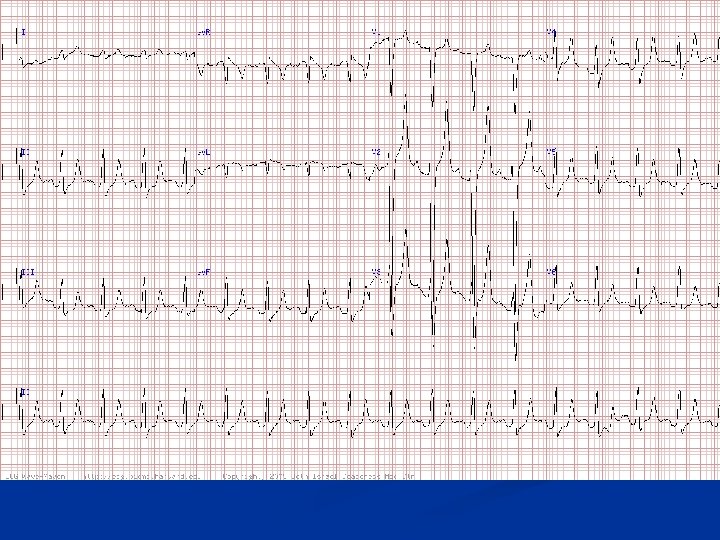

Question #3 n This ECG is most consistent with which diagnosis? A. B. C. D. E. Acute anterior myocardial infarction Accelerated idioventricular rhythm Marked hyperkalemia Marked hypercalcemia Systemic hypothermia

Hyperkalemia The K+ was 10. 5 m. Eq/L in a patient with renal failure n Note the wide QRS complexes with no evident P waves n CK was normal and ST elevations were likely due to hyperkalemia. (Note: The apparent spike after the second QRS complex is an artifact. ) n